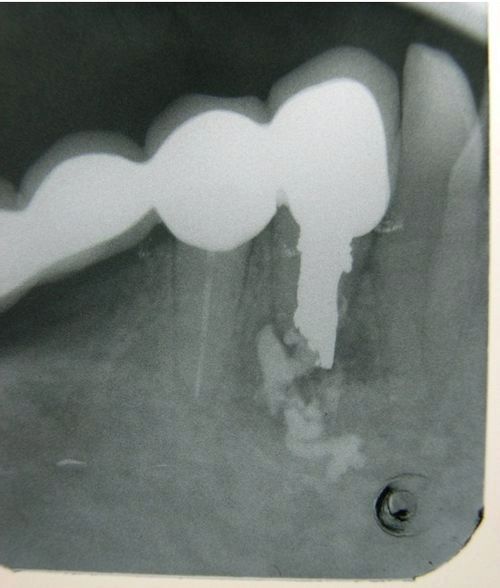

Наявність кіст було підтверджено рентгенограммой 36.

R-фія 36. Кісти під обома країнами 36. Верткальний дефект мезиальной поверхні заднього кореня 36.

R-фія 36. Через місяць після початку лікування 36. ГАНГ сконцентрований в дефектах коренів 36.

На рентгенограмі 36 видно відсутність кіст під корінням 36.Вкладкі фіксовані на антибактеріальний інтерметалідних композит.

R-фія 36. Вкладки фіксовані.